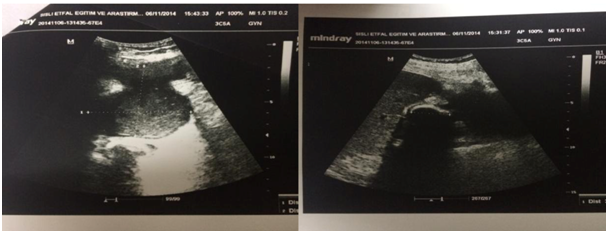

A 61-year-old man, with a known medical history of insulin dependent diabetes mellitus, admitted to the emergency department with the complaints of nausea, vomiting and intermittent abdominal pain in the right upper quadrant for ten days. In the inspection of abdomen an 8 cm hyperemic mass and tenderness on the right hypochondrium was detected (Figure 1). There was no history of trauma and surgical procedure. The patient’s overall health condition was not gravely affected, showing a temperature of 38,4 °C, heart rate of 110 bpm and arterial blood pressure of 125/75 mmHg. Physical examination of patient reveals bowel sounds were normoactive and right upper abdominal quadrant appeared tender at palpation with rebound tenderness. Laboratory results showed only an elevated white blood cell count 15 x 106/l (normal range:3.8-10, 0 x 106/l ). C – reactive protein was 354 mg/l (normal range:0-5 mg/l). Liver function tests were within normal limits. The abdominal ultrasonography revealed a thickened gallbladder containing multiple calculi and a 70X69 mm of abdominal abscess that is originating from the gallbladder and showing extension to the subcutaneous tissue of the abdominal wall (Figure 2). Also, sonographic Murphy sign was found to be positive. Abdominal computed tomography confirmed the ultrasonographic findings and also showed communication between the gallbladder and the subcutaneous collection (Figure 3). The patient underwent right subcostal laparotomy; the fistula track was found and excised. The gallbladder was freed from the adhesions to the abdominal wall, and the open cholecystectomy procedure was performed. After the subcutaneous abscess was drained, a Jackson-Pratt drain tube is inserted into the sub-hepatic region. The patient was discharged on the fifth postoperative day without any complications.

Figure 2 The transabdominal ultrasonography scan of the abdomen: Calculi in the gallbladder and abdominal abscess in the subcutaneous tissue.